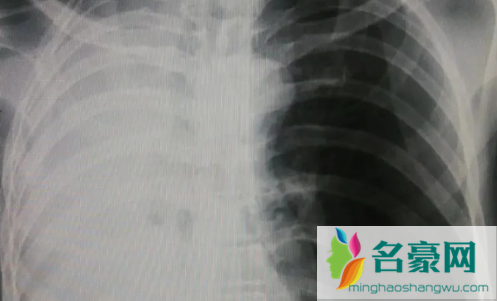

白肺是目前很多人比较担心的问题,因为肺部感染比较严重的话,可能会出现白肺的情况,而不少人不知道白肺到底是什么。那么,白肺症状表现有哪些?白肺治疗要多久能恢复?一起来看看名豪网带来的详细介绍吧!

白肺症状表现有哪些

1、典型症状:本病最典型的症状是呼吸困难,如果是轻度白肺病,呼吸困难通常发生在剧烈活动时,因此常被忽视,或误诊为其他肺部疾病。随着病情发展,患者在静息状态下也可能出现呼吸困难。